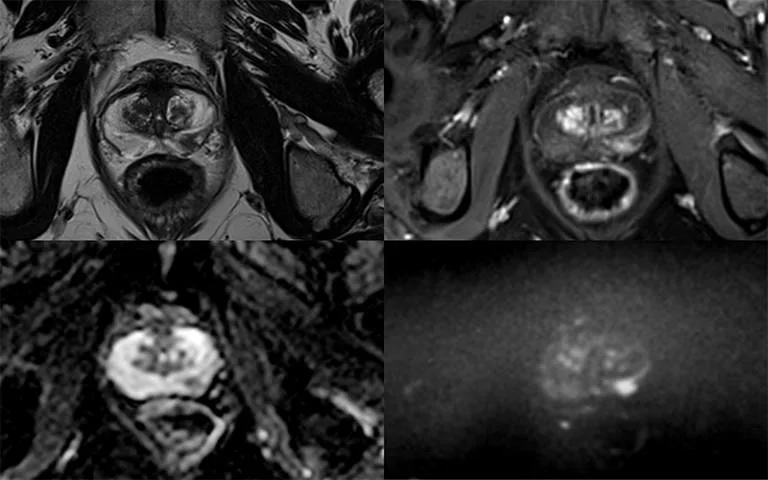

Feature: Accelerating prostate cancer diagnosis

The support of The John Black Charitable Foundation is providing the basis for clinicians to diagnose prostate cancer faster, positively impacting millions of men across the world.